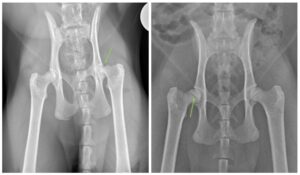

Femoral capital physeal fractures (FCPF) are fractures that occur through the growth plate located at the femoral head (Figure 1): the “ball” of the ball and socket joint of the hip. While both dogs and cats can develop fractures in this area, it more common in the feline population. While the majority of fractures are accompanied by a history of some sort of traumatic event, cats, and a small population of dogs, may develop this particular fracture without any such history, a condition known as a slipped capital femoral epiphysis (SCFE); these fractures are thought to occur secondary to abnormal development of the growth plate.

When presenting your pet for an initial appointment for concerns of lameness or pain, your primary care or emergency veterinarian will likely recommend starting off with radiographs (colloquially termed x-rays). Luckily, FCPFs can usually be diagnosed using this technique in isolation, but occasionally, for subtle cases, additional imaging in the form of a Computed Tomography (CT) scan may be required.